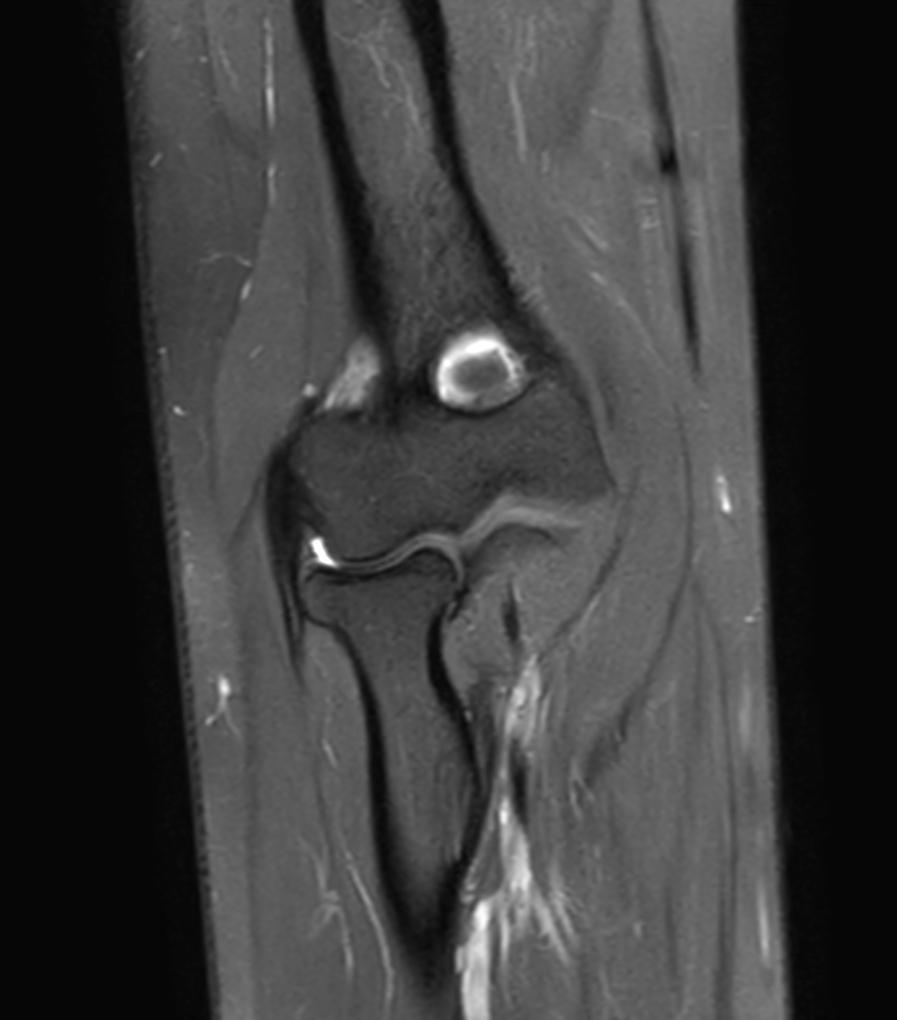

Coronal PDw SPAIR